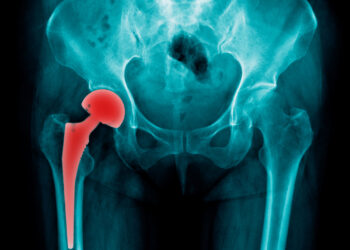

Skaityti daugiauDetailsŠlaunikaulio kaklo lūžis yra dažniausias klubo lūžio tipas. Dažniausiai tai atsitinka dėl stiprios traumos – pavyzdžiui, stipriai nukritus, patekus į...